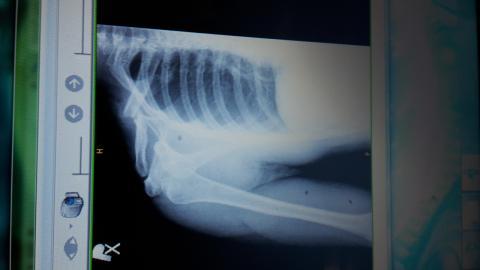

Zlomenina

Pro větší náhled klikněte na obrázek

palkox - 30.6.2015 21:34:06 Dobry vecer,chcel by som sa spytat ci sa da zoperovat zle zrastena zlomenina claviculy? Som uz vyse 2mesiacov po zlomenine a mi to pomerne vadi a k tomu mi trpnu prsty da sa po takej dlhsej dobe operovat znova lamat a drotovat?

Dobrý den, i taková možnost tu existuje, bohužel její výsledky nemusí být dobré, není to jako u čerstvé zlomeniny. Divím se, že takovou zlomeninu vám neoperovali a nechali jen srůst. Zkusila bych ještě rehabilitace na uvolnění pohybů a vitamin B k posílení regenerace nervu.